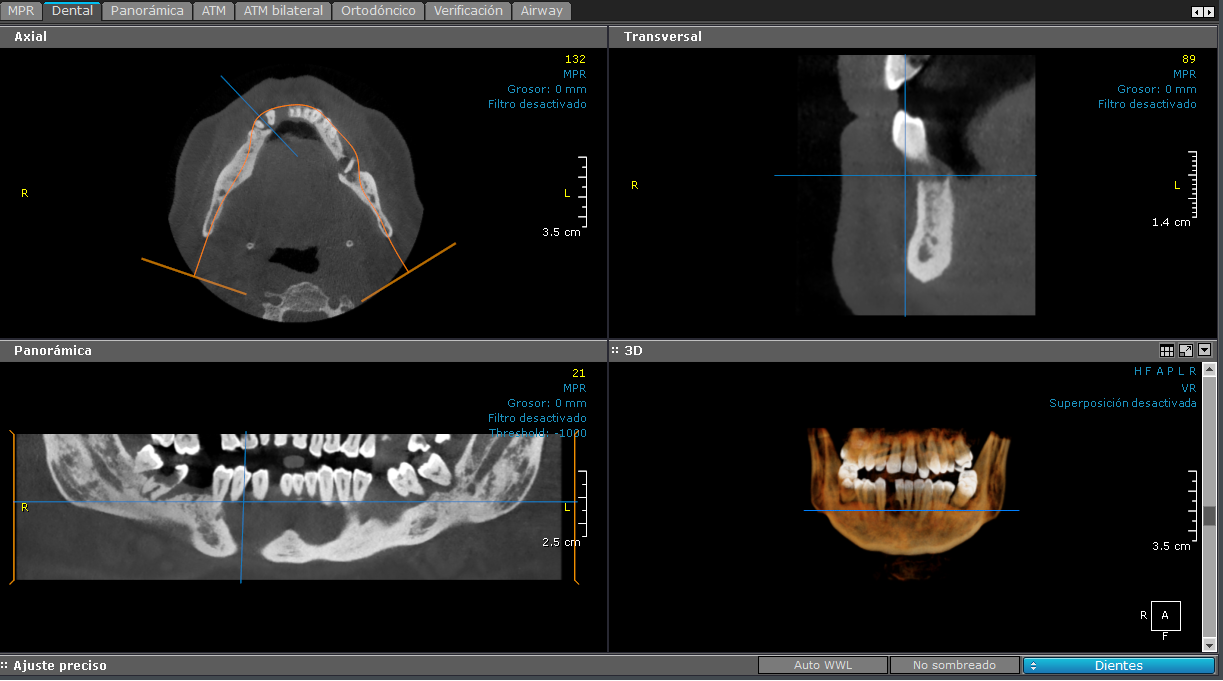

3D - Maxilar Inferior

Maxilar Inferior

Esta imagen está centrada en el maxilar inferior.